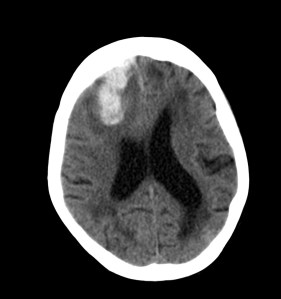

Se investiga un poco más y se descubre que el paciente había acudido diez días antes, también con cierta clínica de debilidad en hemicuerpo izquierdo, y se le realizó un TAC de cráneo. Observemos por tanto el estudio previo:

Pues bien, ante los hallazgos descritos, se clarifica que estamos ante un paciente el cual no tiene una masa y que ha sufrido una lesión isquémica hace diez días. Ahora, sobre dicha lesión, tenemos una imagen con un aumento de densidad que sugiere sangrado por una parte y otra hipodensidad en la perifería que correspondería a un edema. Por tanto, descartamos un sangrado intraparenquimatoso de novo. El paciente tiene más de 65 años, no es hipertenso, la imagen del sangrado no es de alta densidad, lo que se opone a una fase aguda o hiperaguda, y tenemos el TC de cráneo previo donde ya se advertía un proceso de tipo isquémico. Por tanto, nos quedan dos opciones, o estamos ante un resangrado de un ACV o estamos ante una Perfusión de lujo.